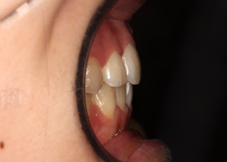

上前歯が前方へ突出しており、特に右側の突出が大きいです。また上下の前歯が噛み合っていません。

上下とも前歯のでこぼこが顕著です。

上下前歯にでこぼこがあり、特に右側の上前歯の突出が目立ちます。